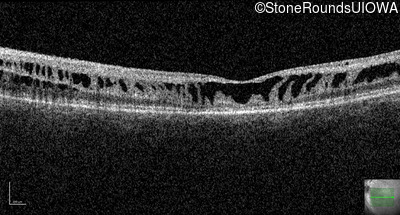

Optical Coherence Tomography - Right - 10/40

Exemplar / OCT Stack